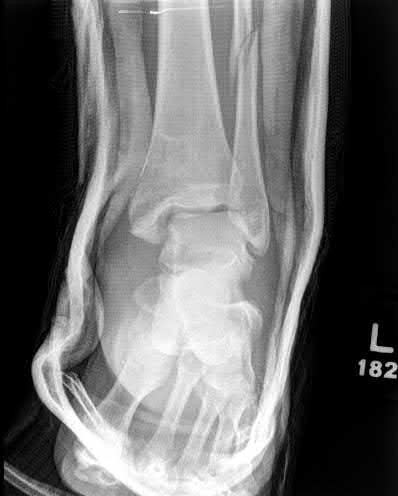

A 25-year-old female is involved in a motor vehicle collision. She presents with the isolated injury seen in Figures A through D. Her leg is swollen but her skin is intact. She has no clinical signs of compartment syndrome. Which of the following treatment options will allow for maintenance of fracture alignment and minimize the risk of soft tissue complications?

The patient presents with a closed distal third metaphyseal-diaphyseal distal tibia fracture with simple intra-articular extension. Immediate intramedullary nailing along with percutaneous fixation of the articular component provides appropriate restoration of length, rotation and alignment and minimizes the risk of wound complication.

Displaced distal third tibia fractures may be associated with simple intraarticular extension. Operative treatment of intra-articular distal tibia fractures has historically been performed with open reduction and internal fixation. Early open reduction and plate fixation of pilon fractures has been associated with high rates of infection and wound complication. In select patterns with simple articular extension, percutaneous screw fixation and medullary nailing may provide appropriate reduction with minimal soft-tissue risk.

Figures A and B demonstrate a distal third tibial shaft fracture with simple intra-articular extension. The axial and coronal CT cuts in Figures C and D further clarify the articular injury. Illustrations A and B demonstrate a comminuted distal third tibial fracture with simple intra-articular extension. Illustrations C and D are fluoroscopic images of the same injury after intramedullary nailing and percutaneous fixation of the articular component.